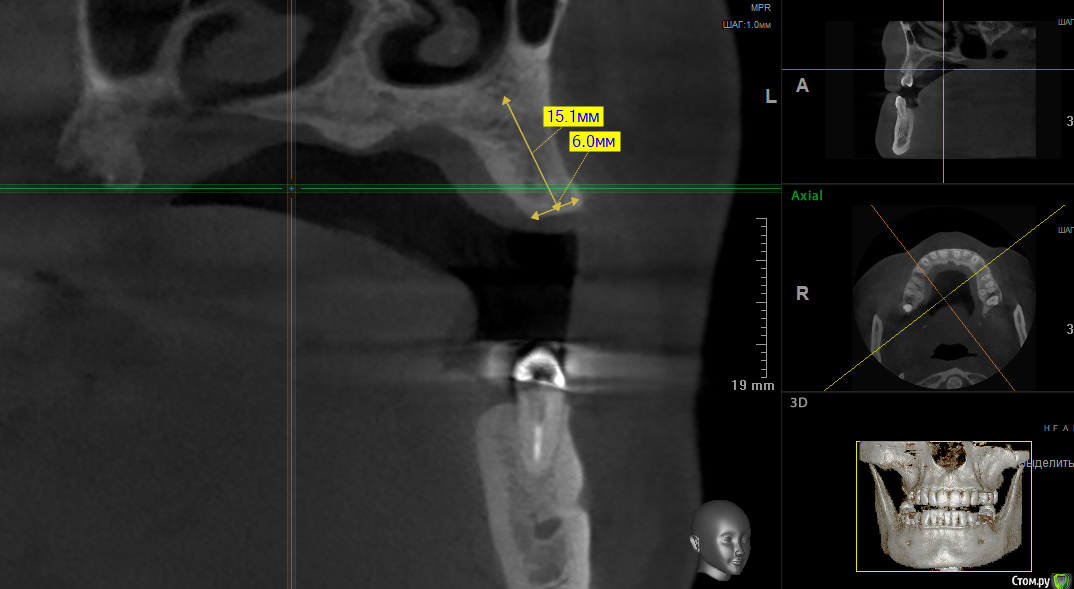

kramer Опубликовано 16 мая, 2018 Поделиться Опубликовано 16 мая, 2018 Коллеги, здравствуйте. Подскажите, пожалуйста, какое положение имплантата будет наиболее оптимальным? Область 24. Ставить под углом и в последствии угловой абатмент или прямо, но с риском для кортикалки? или нечто третье? Ссылка на комментарий

kramer Опубликовано 16 мая, 2018 Автор Поделиться Опубликовано 16 мая, 2018 Срез не верный. Переделал. Как-то так. Ангуляция имеется Ссылка на комментарий